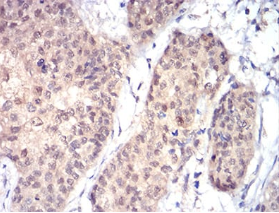

RAD23A Mouse Monoclonal antibody[3E3F4]

Immunogen:    Purified recombinant fragment of human RAD23A (AA: 1-363) expressed in E. Coli.

IHC    1/200 - 1/1000